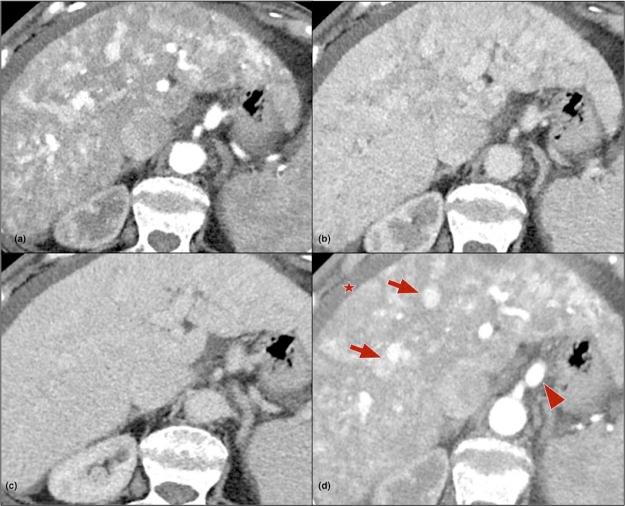

Hereditary hemorrhagic telangiectasia or Osler-Weber-Rendu syndrome is a rare autosomal dominant vascular disorder characterized by epistaxis, mucocutaneous telangiectasias, and arteriovenous malformations affecting various organs and systems. The liver is a commonly involved organ (74% of patients with hereditary hemorrhagic telangiectasia), although symptomatic liver disease is quite infrequent. In symptomatic cases, clinical manifestations relate most commonly to the predominant type of vascular shunting present (arteriovenous, arterioportal, or portovenous). Clinically, liver disease can manifest as a high-output cardiac failure, portal hypertension, or biliary disease. Imaging plays an important role in diagnosis, characterization, and follow-up of liver involvement, with ultrasound, computed tomography, magnetic resonance imaging, and angiography being useful in this context. We present a case of congestive cirrhosis with florid liver findings in a patient with Osler-Weber-Rendu syndrome. Imaging findings that clinched the diagnosis are reviewed. A brief literature review is also provided.